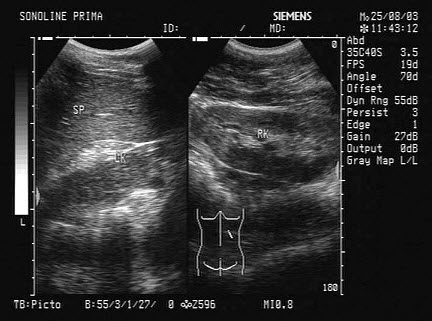

如图所示,双肾结构清晰,左肾体积小,该病例最可能诊断是( )

A:肾发育不良

B:肾萎缩

C:慢性肾炎

D:肾结核

E:慢性肾衰